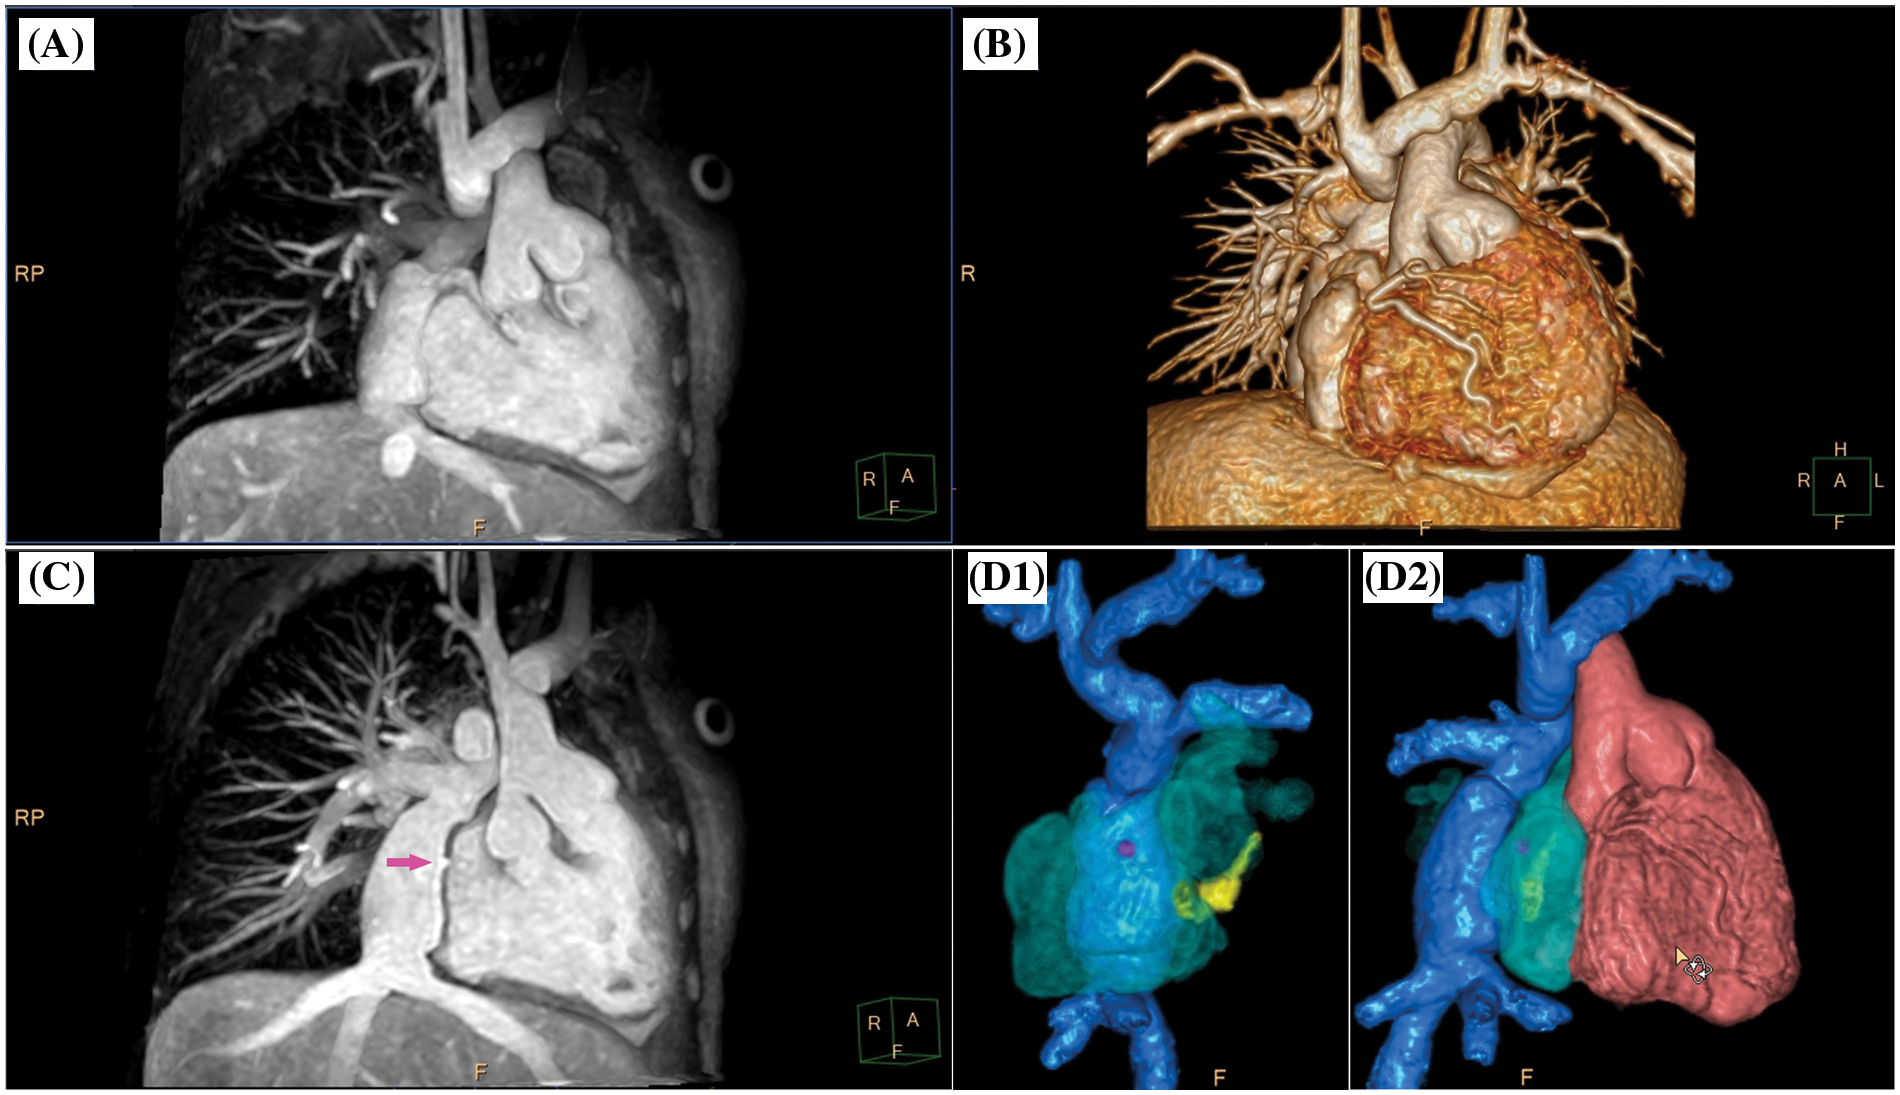

Figure 3: Clinical case example I. (A) Volume-intensity projection; (B) volumetric surface rendering; (C) angulated volume-intensity projection for depiction of fenestration site (right anterior oblique angulated view, magenta arrow); D1 and D2, composite volumetric surface rendering of vascular compartments/endoluminal cavities including intracardiac lateral tunnel (blue), fenestration (magenta), atria (transparent green), coronary sinus (yellow) and single ventricle (red). Please refer to video 1 for a fully animated case presentation

Video 1 (.MP4 file)

Clinical case example I (same case as shown in Fig. 3)

Three-dimensional whole heart imaging using nonselective balanced SSFP with compressed SENSE (nsWHcs) in an 11-year-old boy (bodyweight, 20 kg; heart rate, 65/min; propofol sedation) with a single ventricle and total cavopulmonary connection with intracardiac lateral tunnel prior to radiofrequency ablation of ectopic atrial tachycardia. Note the flow-independent homogeneous blood pool signal in all vascular compartments/endoluminal cavities resulting in clear depiction of the fenestration site of the intracardiac lateral tunnel which is crucial for guidance of atrial catheter access.